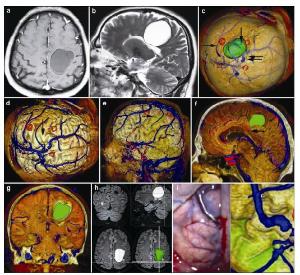

20170308101048  Figure 8 Magnetic resonance imaging, reconstruction images, surgical incision, 3D view, and actual operative view in a 51-year-old male patient with a vascular malformation in right frontal lobe. (a, b) T1 enhancement scan: The cyst presented as no enhancement; (b) T2 scan: The cyst presented as high signal. (c) 3D reconstruction (skull semitransparent): The cyst (vertical single arrow) located behind the coronary suture (horizontal double arrow) and the markers are around the cyst. The superior sagittal sinus and superior cerebral veins (horizontal single arrow) are faintly visible. (d) 3D reconstruction (do not show the skull): The cyst (vertical single arrow) is faintly visible and locates anterior to one superior cerebral vein. The veins on the surface of the brain can be seen clearly. (e) 3D reconstruction (lateral view): The cyst (horizontal single arrow) is anterior to one superior cerebral vein and locates under the motor cortex. (f) Sagittal cutting: The corpus callosum (horizontal single arrow) is compressed by the cyst. (g) Coronay cutting: The lateral ventricle and corpus callosum are compressed by the cyst. (h) 3D view: The images of 3D reconstruction are consistent with that of flair MRI. (i) The comparison of intraoperative situation and 3D reconstruction: The intraoperative situation is consistent with 3D reconstruction images.